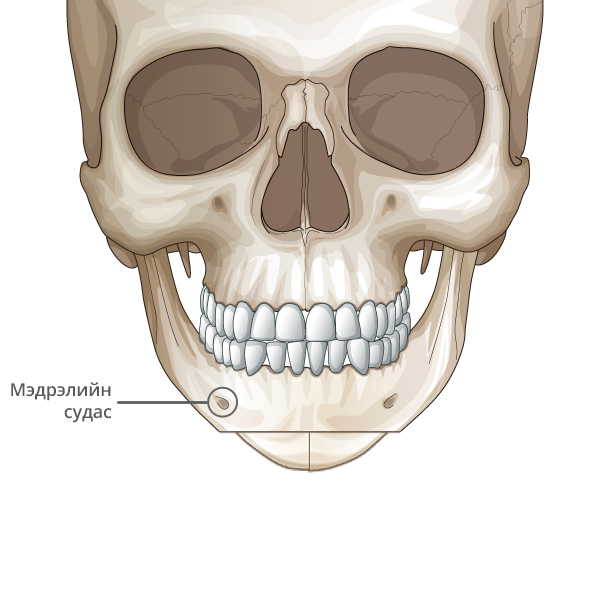

Мэдрэлийн судаснаас зайлсхийж, эрүүний төгсгөлд зүсэлт хийнэ.